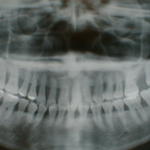

しかし、虫歯がさらに進行した場合は歯をささえる歯槽骨(しそうこつ)を侵し歯ぐきがはれたり、膿がたまったりして場合によっては抜歯となることも少なくありません。

そうならないためには他の病気と同じように早期発見、早期治療が虫歯治療においても大切なこととなります。

歯周病の治療

原因が複雑なため完全な治療は難しいのが現状ですが、まず第一に行うことは歯の周囲にくっついている細菌のすみかである歯垢(プラーク)と石を徹底的に除去することです。

歯垢、歯石は歯についた食べかすが固まってできるものですから、食後の歯磨きを怠らないことが歯垢、歯石の沈着防止につながります。

歯周病は油断するとすぐ再発することが多いので、定期的な歯石除去などのメンテナンスを続けることが大切です。